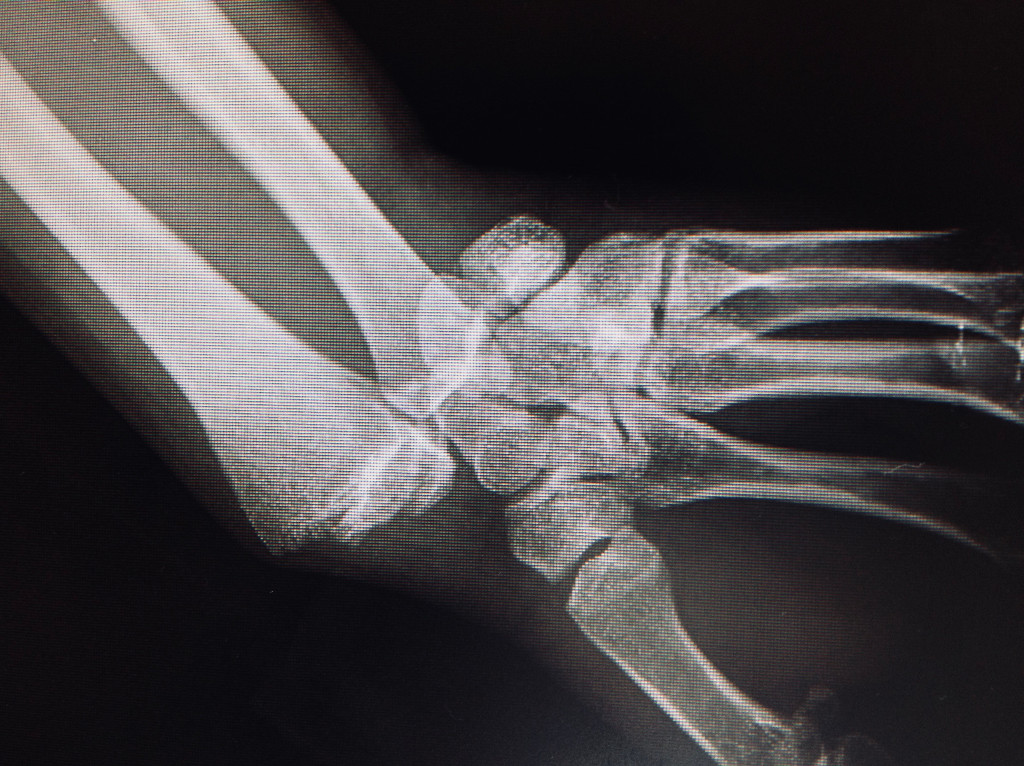

- Embrochage : consiste à passer des broches (d'un diamètre de 1,5 millimètres) à travers de

petites incisions réalisées dans la peau jusque dans l'os. broches sont enlevées au bout de

5 semaines. Ces broches nécessitent souvent une immobilisation complémentaire par

attelle.

Dans le cas des fractures non déplacées, il est possible de procéder à un traitement orthopédique par immobilisation du poignet avec attèle pour 3 mois. La durée d'immobilisation est liée à la lenteur de consolidation de ce petit os. Toujours dans le cadre des fractures non déplacées, il est possible d'améliorer le confort en pratiquant une intervention chirurgicale quasiment sans cicatrice (percutanée), qui consiste à visser en compression le scaphoïde. Cette intervention chirurgicale a pour avantage de ne pas immobiliser le poignet, et de débuter immédiatement une rééducation. En cas de fracture déplacée du scaphoïde, il faut réaliser une intervention chirurgicale pour réduire la fracture et la maintenir en place par une vis en compression. Cette intervention se fait par une voie d'abord percutanée ou quand ceci n'est pas possible par une technique à ciel ouvert et après l'opération il est habituel de commencer une rééducation immédiate.

- En cas de fracture du scaphoïde, un éventuel brochage ou vissage de la fracture pourra être contrôlé parfaitement par cette technique.